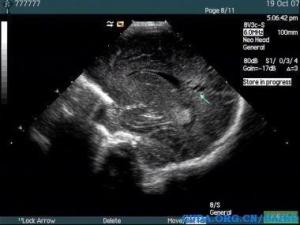

超声诊断

脑白质软化早期超声可见脑室周边白质回声增强,边界不清,没有占位效应,如果没有这方面的意识,此时容易漏诊,因此在颅脑超声检查时,能够显示各个脑室的切面均需观察其附近脑白质回声是否均质,有无回声增强,随着时间推移,其内可见液性囊区,比较容易被超声发现!新生儿缺血缺氧性脑病、颅脑损伤为常见病因。

一般这种患儿多在新生儿期检出,有颅内感染、宫内感染或者产伤的病史,颅脑超声检查时需注意脑白质回声是否均质,早期病变与周围正常组织对比度不是很明显,易漏诊![1]